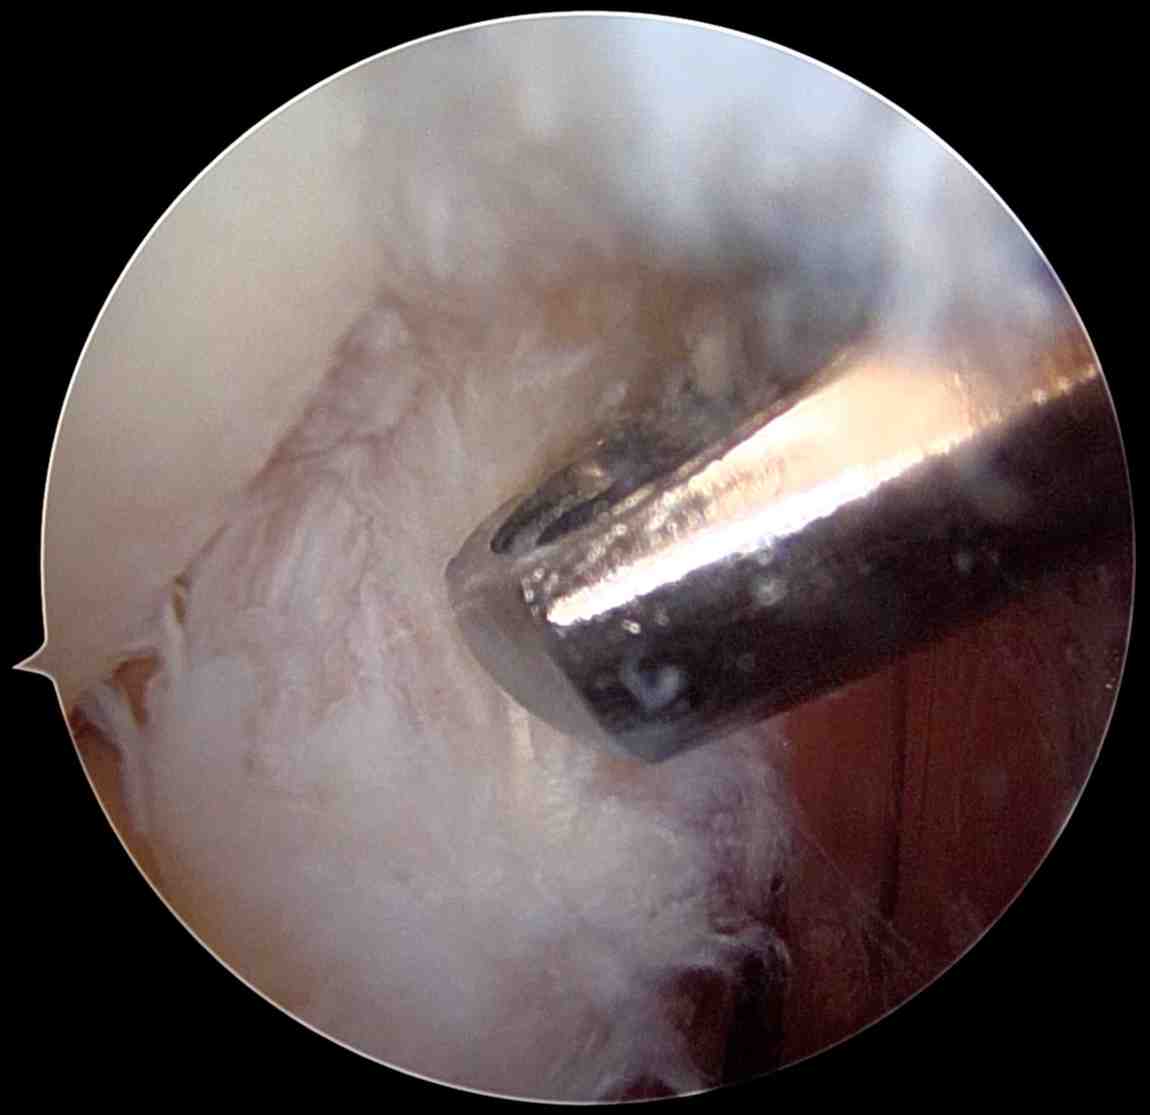

- Arthroscopic Surgery

- Minimally invasive; uses tiny incisions and a camera (arthroscope).

- Allows the surgeon to view inside the joint and remove damaged tissue.

- Less invasive, possibly shorter recovery, but technically more complex.